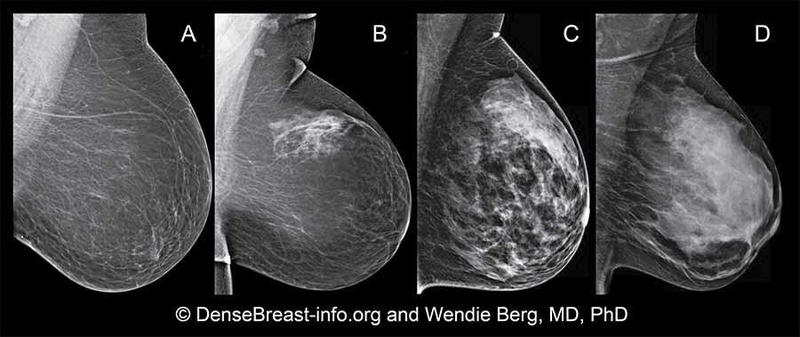

Chụp nhũ ảnh sử dụng máy X-quang đặc biệt để phát hiện khối u và các bất thường khác trong mô vú. Đây là loại máy phụ trách chụp X-quang tuyến vú kỹ thuật số và chụp tổng hợp vú kỹ thuật số, còn được gọi là chụp quang tuyến vú 3D. Các chuyên gia cho biết cả hai đều hoạt động hiệu quả.